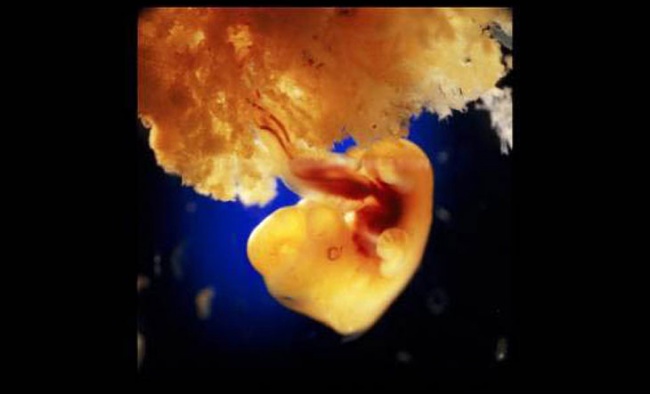

Formación de la placenta, en el día 40 de la gestación.